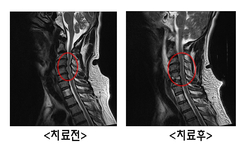

PMC박병원, 혈관 넓히고 경추 유합술 시행

- 2017-03-07 15:21

- 김선호 기자